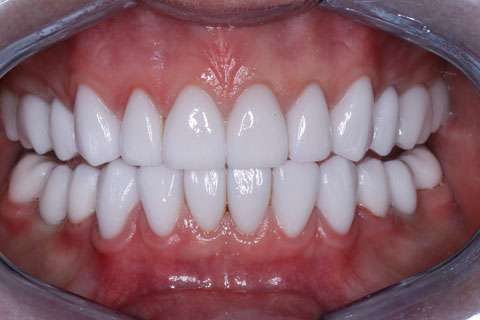

Проведена ортопедическая реабилитация.

Фронтальная группа зубов верхней и нижней челюстей – установлены виниры.

Жевательная группа – восстановлена коронками из диоксида циркония, в том числе 3.5, 4.5 – коронки на имплантатах.